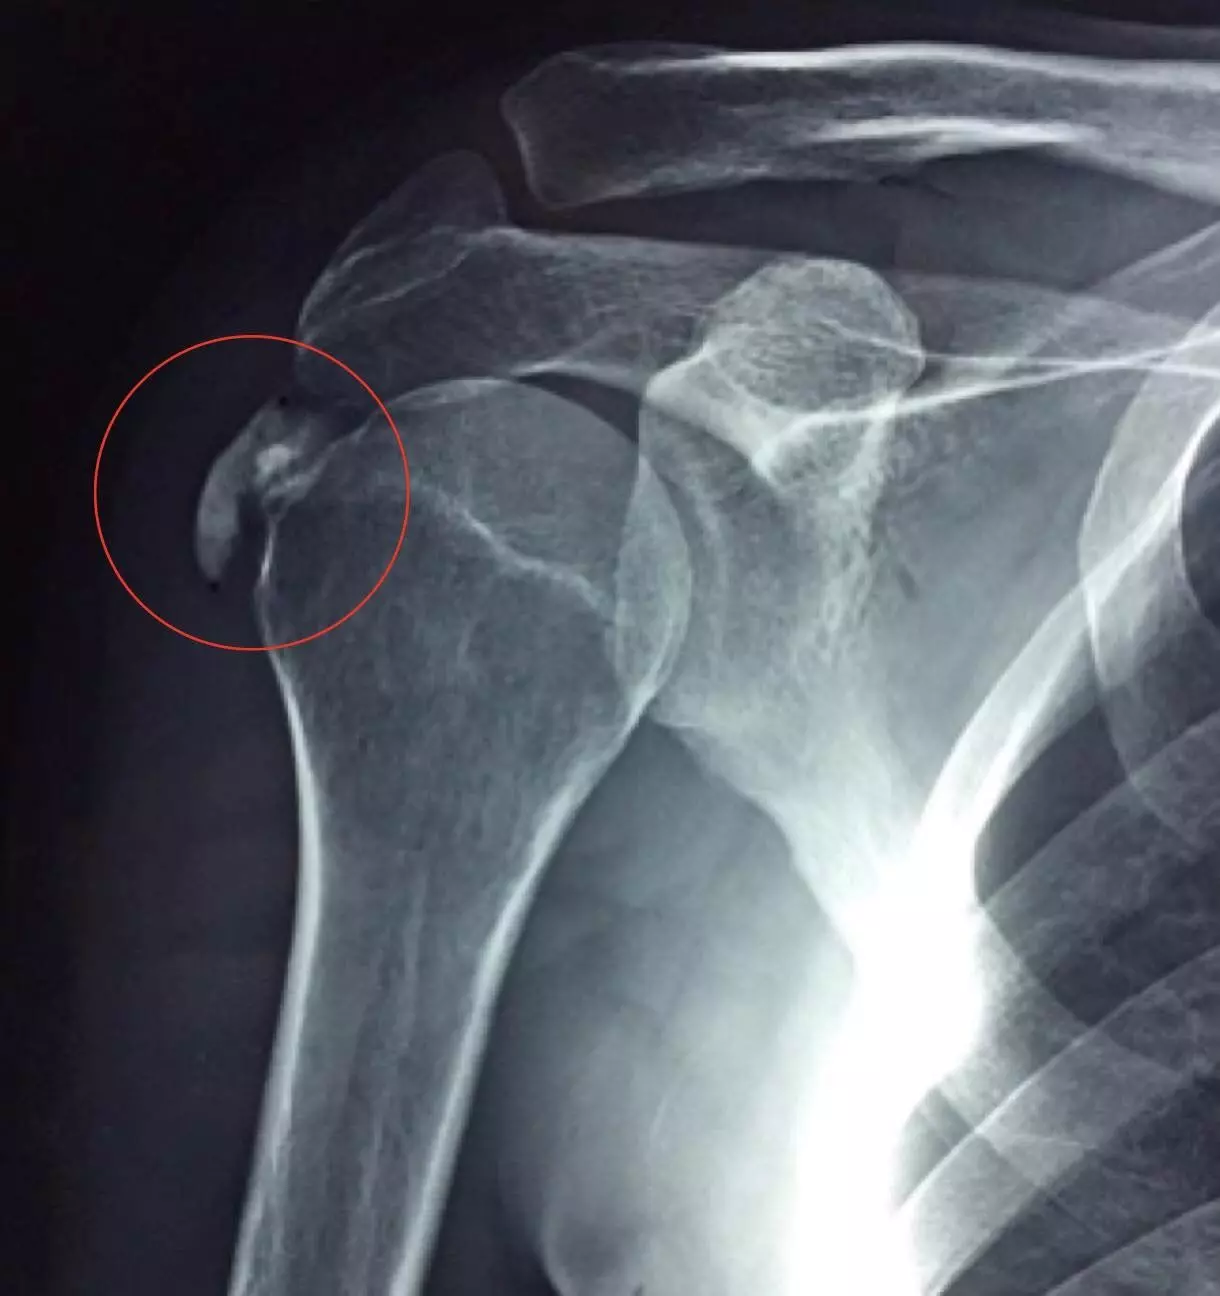

Diagram - An X-ray of a shoulder dislocation with Bankart and Hill-Sachs lesions

Creative commons source by Mikael Häggström, M.D. [CC BY-SA 4.0 (https://creativecommons.org/licenses/by-sa/4.0)]

- Bankart lesion- tear of the glenoid labrum

- Hill-Sachs lesion- dent in the humeral head caused by the lip of the glenoid fossa impacting it during the injury.